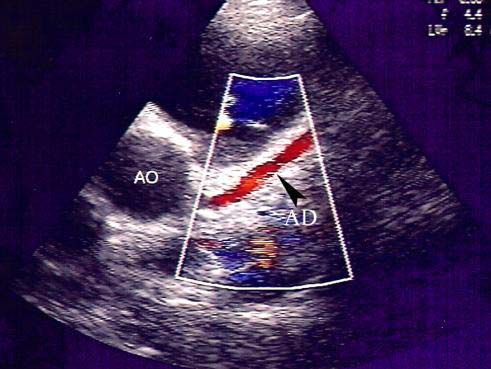

Ну наконец-то, а то я уже сам начал сомневаться.В данном случае мы видим синий поток (направлен от датчика) со стороны АК - это коронарно-легочная фистула, и второй поток от бифуркации ЛА (ближе к левой ветви) - это ОАП

Точно, виден поток КЛФ, молодец SWETLANA!В данном случае мы видим синий поток (направлен от датчика) со стороны АК - это коронарно-легочная фистула, и второй поток от бифуркации ЛА (ближе к левой ветви) - это ОАП

Сергей, вы присмотритесь, поток не меняет свой диаметр на всем протяжении...

В фистуле не обязательно турбулентный кровоток, очень часто бывает небольшой скорости кровоток и небольшого объёма.Поток при фистуле разноцветный, мозаичный, назовите, как хотите, но не однотонный, как в данном случае. Да еще такая локализация. Потому , лично у меня. глаз за это не цепляется. Не фистула это.

На мой взгляд поток не меняет диаметра из-за своих малых размеров, а не цепляет глаз из-за особенности своего хода (синий поток из фистулы сливается с синим потоком в стволе ЛА).

Как писала Наталья, желательно бы поймать спектр потока импульсно-волновым допплером. Ну и по любому ребенок будет консультироваться кардиохирургами в связи с ОАП.